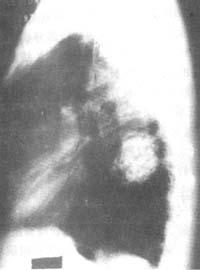

错构瘤的诊断主要依靠X线检查,多数是在X线常规检查时偶然发现的。X线上表现为均匀致密的阴影,也可以不均匀阴影,还可以有钙化,钙化影呈现爆米花状的图案,周边部密度相对较低,可能为脂肪组织。爆米花征是肺错构瘤的特征性表现,但不多见而且不是肺错构瘤所独有(图1)。

图1 肺错构瘤